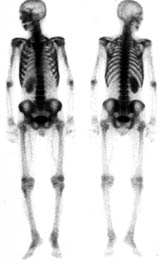

| 第196回定例研究会(1997.6) 骨シンチ『異常集積の少ない骨転移』 | 神奈川県立がんセンター | 小野 慈 |

| 第196回定例研究会(1997.6) 骨シンチ検査の基礎講座 | 神奈川県立循環器呼吸器病センター | 大島 正行 |

(2)compartment解析に関しては代表的なものは、1-compartment model(秀毛らの非線形model(Fig.3)に始まるが、篠原が報告した如く線形modelでの短時間に演算可能な方法でも実用的であった。Veraらが唱えた3-compartment modelは採血を伴うmodel式を利用しており、やや煩雑さを伴っている。河らが提唱した5-compartment modelは複雑な計算式を必要としているが、肝最大除去率(Rmax)を算出可能である。(Fig.4)病的 hotなし。 | 第12胸椎に骨溶解像。 | 第12胸椎に 低信号域。 |

![]() | ![]() | ![]() |

| ・全身シンチ | ||||

| コリメータ | 収集マトリックス | ピクセルサイズ | 収集条件 | 撮像方向 |

| mm/Pixel | (スキャンスピード) | |||

| LEHR | 256×1024 | 2.0 | 10〜15cm/min | ANT,POST |

| 512×2048 | 1.0 | |||

| ・部分シンチ | ||||

| mm/Pixel | (カウントorタイム) | |||

| LEHR | 512×512 | 0.6〜1.0 | 1000K(8分) | 異常部位多方向 |